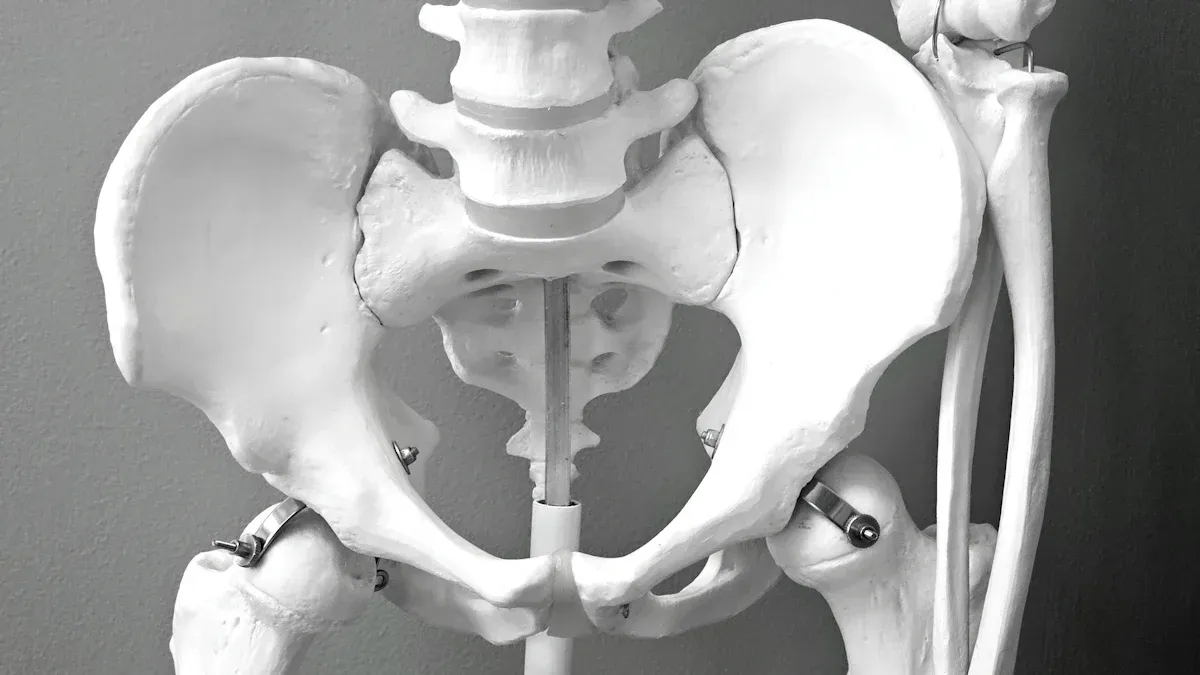

Neck misalignments are a big reason for cervical vertigo. If your neck is not lined up right, it can cause problems:

- The brainstem may get pressed, which can mess up signals between your brain and body. This can make you lose your balance.

- Less blood may reach your brain, making you feel dizzy or lightheaded.

- The fluid around your brain and spine may not flow well, which can make symptoms worse.

- Nerve signals may not travel right, causing dizziness or spinning feelings.

If your head leans forward, your neck gets more stress. This can make your symptoms worse and change how your muscles feel. Keeping your neck in the right spot helps your body work better and can help you feel less dizzy.